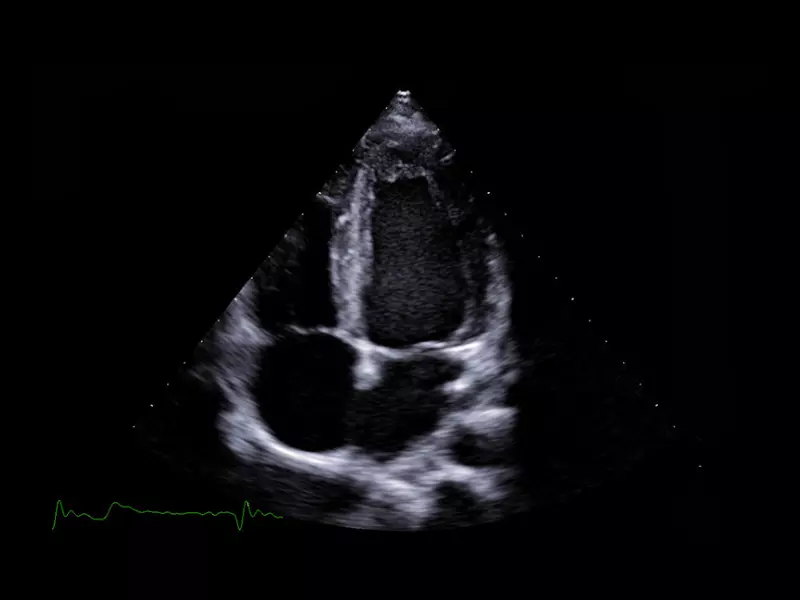

Q7 - CV Cardio B-mode

Q7 - CV Cardio B-mode

Q7 - CV Cardio B Mode 2

Q7 - CV Cardio B Mode 2